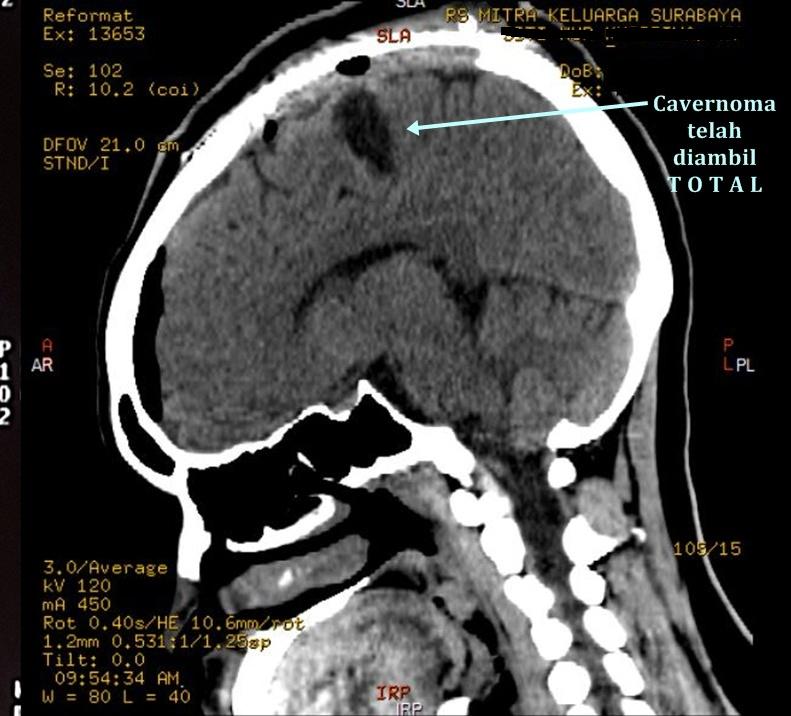

Operasi bedah mikro pengangkatan tumor pembuluh darah ini adalah satu-satunya cara pengobatan. Kelainan ini tidak radiosensitif, artinya cavernoma tidak bisa disinar dan tidak bisa dilakukan tindakan endovaskuler. Operasi pengangkatan cavernoma bersifat kuratif dan tekniknya bergantung pada keadaan pasien sebelum operasi, berdasarkan anatomi, letak, dan gejala yang ditimbulkan.

Cavernous Malformation terutama yang terletak pada permukaan otak, bisa diangkat secara aman dengan operasi. Kelainan ini dapat dipisahkan dari otak dan diangkat tanpa mengganggu jaringan otak normal karena biasanya batasnya jelas dan bila pernah pecah, akan ada batas darah yang mengelilingi lesi (hemosiderinrim). Bahkan cavernoma pada batang otak juga dapat diangkat dengan aman tanpa menimbulkan kelainan saraf lainnya (deficit neurologis).

Tim Bedah Saraf serebrovaskuler di BSC Mitra Keluarga memberikan solusi kesembuhan yang sudah teruji dan terjamin dalam penanganan kasus-kasus sulit Cavernous Malformation, terutama yang letaknya dalam dan beresiko tinggi. Didukung dengan teknologi yang canggih, pengalaman para dokter yang sudah acap kali menangani kelainan ini, cavernoma bisa disembuhkan secara tuntas.